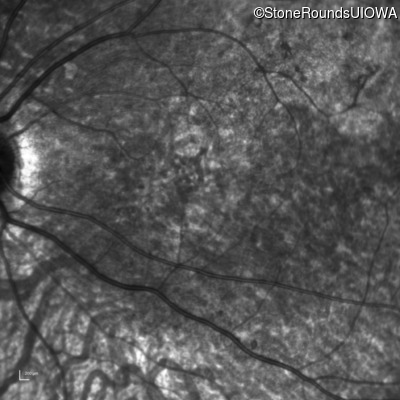

AR Stargardt Disease (IIA)

Age at visit: 8 years

This 8 year old girl had normal vision until age 6 when she failed a school vision screening. That year, she was able to play softball well, but this year she often loses sight of the ball and is often hit by it.

AR Stargardt Disease ABCA4 IVS38-10T>C IVS38-10T>C AR